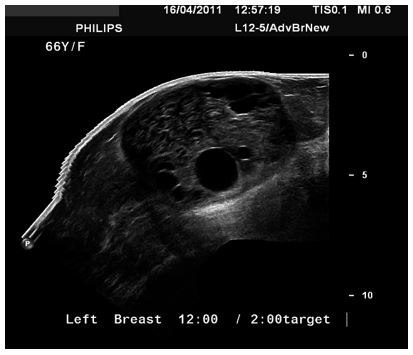

Alamer et al. [13] reported a 66-year-old lady who was known to have hypertension and diabetes mellitus who had presented with a palpable mass within her left breast that was associated with pain over a period of a long time. She did not have any nipple discharge or fever. She also did not have any history of breast trauma, hormone replacement therapy, or a family history of carcinoma of the breast. Her clinical examination showed a large palpable mass which was identified within her left breast with regular borders. Her nipple, areolar, and skin were normal. There was no evidence of palpable lymph node enlargement in her left axilla. Her general examination, systemic examinations and examination of her right breast and right axilla were normal. The results of her investigations including haematology blood tests, biochemistry blood tests, and chest x-ray were normal except elevated serum glucose result. She had a mammogram which showed a large oval and dense mass in the upper outer quadrant of her left breast (see figures 11 and 12). The mass was noted to be lobulated and well-circumscribed in its contours and to have measured 9.2 cm x 7.5 cm. No microcalcification was noted. The nipple, areolar, and skin were normal. The axillary lymph nodes were normal and the right breast was normal. Based upon the mammography examination features of the lump an impression of an usual large dense mass within her left breast was made and coded as BIRAD4A, taking into consideration the age of the patient, and further assessment with ultrasound scan was recommended. The differential diagnoses that were considered included: Phyllodes tumour, pseudo-angiomatous stromal hyperplasia (PASH), and well circumscribed carcinoma of the breast.

She had ultrasound scan of the breast which showed a large heterogeneous and lobulated mass within the upper quadrant of her left breast which had corresponded to the mammographic features. Few internal anechoic cysts were visualized within the peripheral aspects of the breast lesion. Doppler interrogated images did not show any internal vascularity within the mass (see figures 13, 14, and 15). There were no enlarged associated axillary lymph nodes found. She had ultrasound scan-guided biopsy from the lesion. She did have computed tomography (CT) scan for further assessment of the breast lump which did reveal a large hypo-dense mass within her left breast. It also revealed very tiny and thin internal septations were visualized. There was no peripheral enhancement and no internal enhancement. The mass did measure 6.8 cm x 6.2 cm x 9 cm in maximum dimensions (see figures 16 and 17). No axillary lymph nodes were found. The rest of the intra-thoracic and abdominal structures were found to be normal. Pathology examination of the biopsy specimen showed scanty material which had consisted of fragmented eosinophilic membranes that had laminated appearance in keeping with the diagnosis of hydatid cyst. A final diagnosis of hydatid cyst of the breast was made. The patient was referred to the surgeons for surgical excision of the hydatid cyst of the breast at the time of the report of the article. The lesson that needs to be learnt from this case report is the fact that diagnosis of hydatid cyst can be established pre-operatively with careful history taking, clinical examination radiology imaging including ultrasound scan, CT scan, and ultrasound scan-guided biopsy for histopathology/cytology examination which would guide the surgeon to undertake a careful complete surgical excision of the without spillage of the contents of the hydatid cyst.